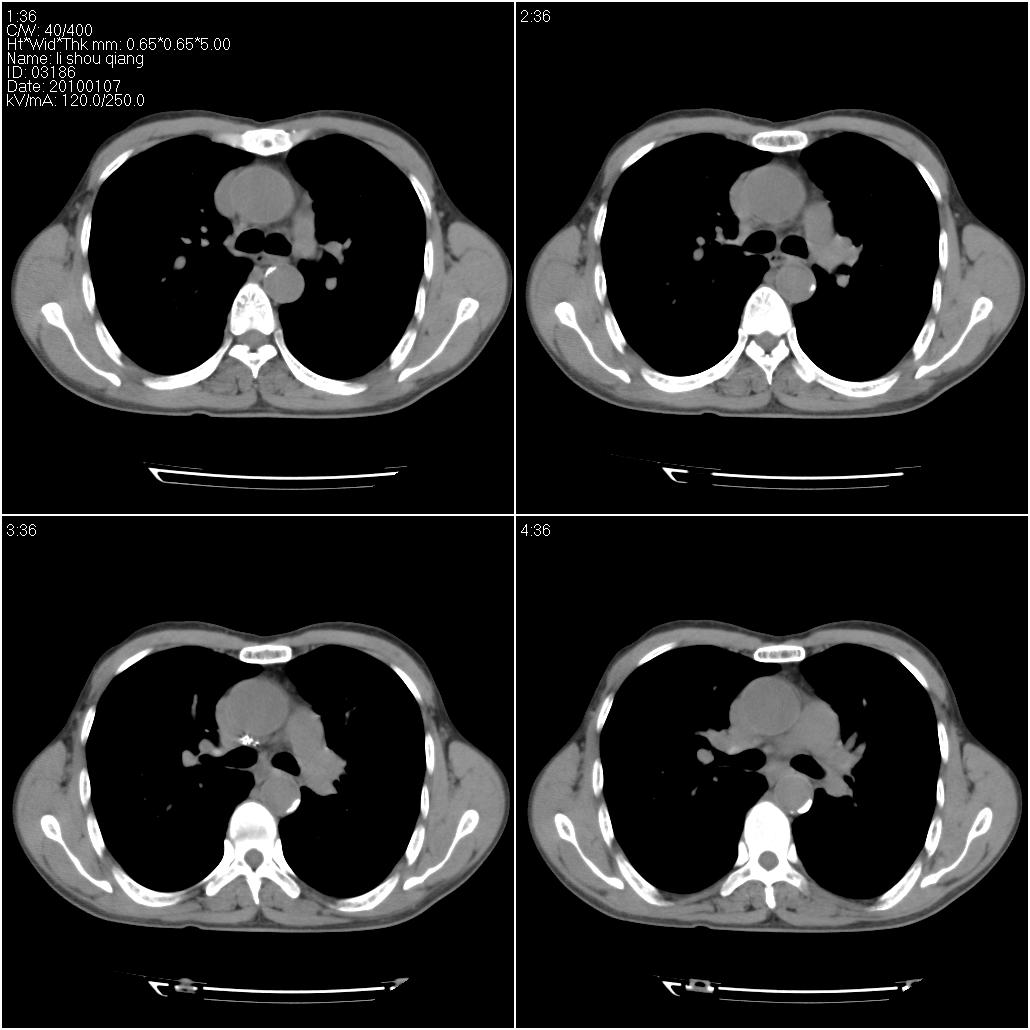

标题: CT24038:男性,58岁。主因咳嗽带血性CT检查。 [打印本页]

标题: CT24038:男性,58岁。主因咳嗽带血性CT检查。

右肺中叶外侧段见一不规则的软组织肿块,边缘可见毛刺,并见厚壁空洞,与胸膜分界欠清。另左下肺见多个小囊状扩张区

1、右肺中叶周围型肺癌并空洞形成。

2、左肺下叶支扩可能性大。

3、建议增强除外主动脉弓息室样动脉瘤。

右肺中叶外侧段可见团块影,外形不规则,内见空泡征。左下肺见蜂窝状低密度透亮影,部分层面主动脉旁瘤样突出。考虑右肺中叶外围型肺癌可能性大,左下肺支气管扩张,主动脉弓瘤样突出。

1、右肺中叶周围型肺癌(内空泡)。

2、左肺下叶支扩,不除外合并肺囊肿。

3、建议冠状位重建除外主动脉弓息室样动脉瘤。